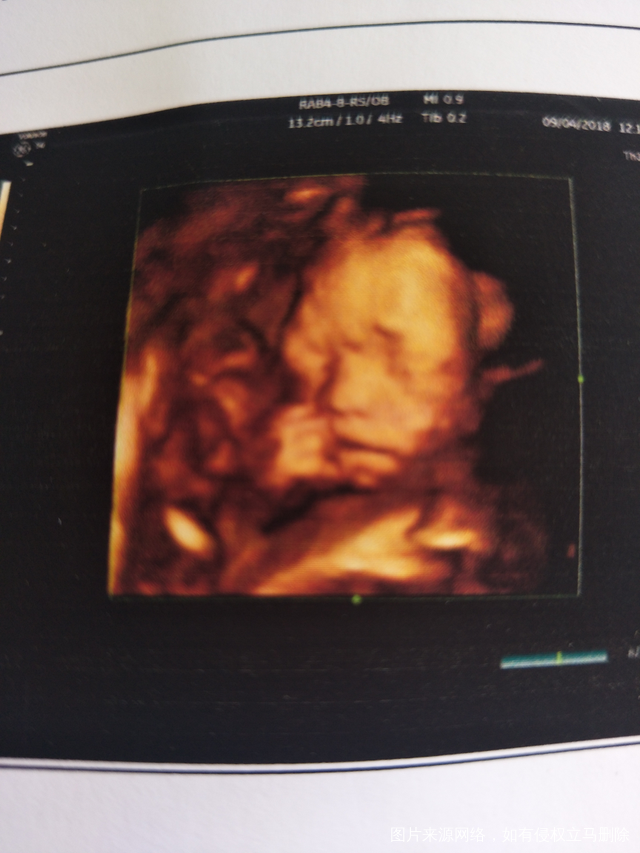

有没有12月份底预产期的宝妈。。。